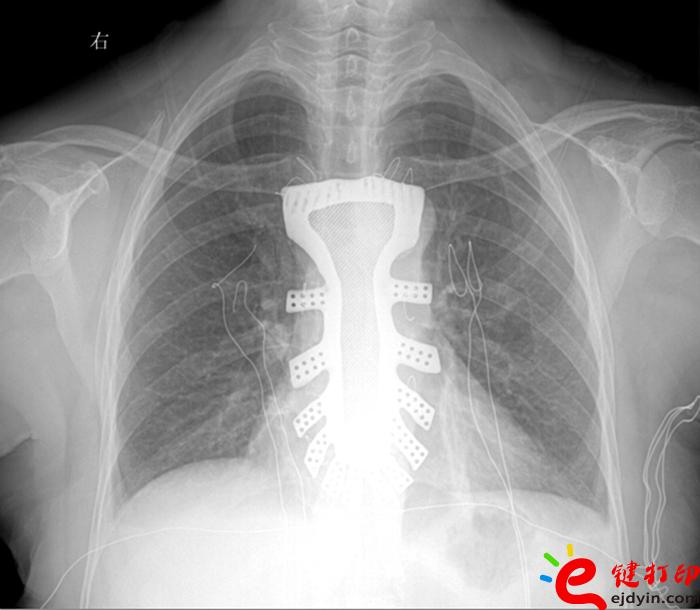

當(dāng)然,“3D打印”的世界遠(yuǎn)不止如此。據(jù)參加大會(huì)的專(zhuān)家和企業(yè)負(fù)責(zé)人介紹,目前“3D打印”已被運(yùn)用在文化創(chuàng)意、文物修復(fù)、生物醫(yī)療、工業(yè)設(shè)計(jì)等多個(gè)領(lǐng)域。如,在航空航天器材上,一些關(guān)鍵零部件采用“3D打印”一次成型,使得其功能更加實(shí)用,重量大幅減少;在醫(yī)療領(lǐng)域,“3D打印”被運(yùn)用于牙齒再造和骨骼修復(fù)等方面,從而使治療更加精準(zhǔn)。